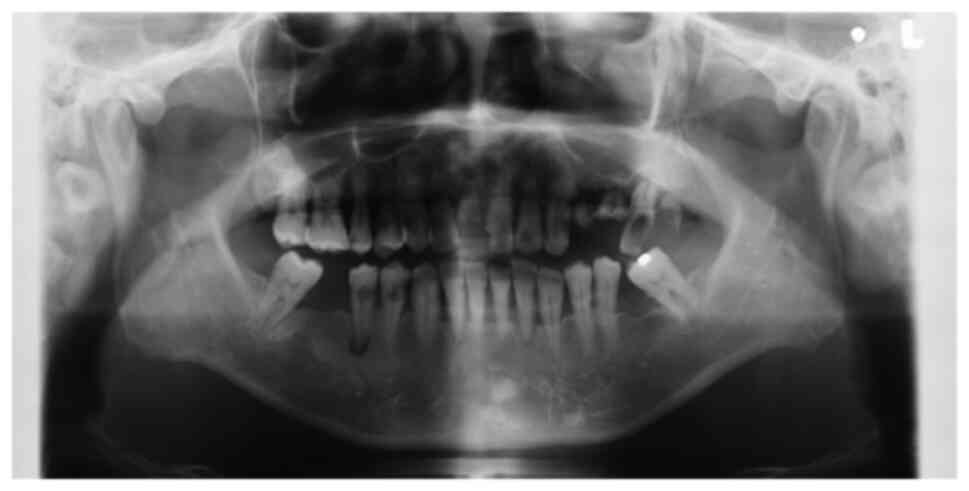

The patient underwent radiological, hematologic and histological examinations, with a differential diagnosis of a gingival tumor invading the maxillary sinus. Orthopantomography and computed tomography (CT) were performed in the radiology department. The orthopantomograms showed horizontal bone resorption in the jaw, particularly in the left maxillary molar root region and around the second premolar (Fig. 2). CT scan of the oral cavity showed a large, poorly demarcated soft tissue mass extending into the left maxillary sinus, with generalized bone resorption around the left second premolar and the base of the maxillary sinus (Fig. 3). CT scans of the chest and abdomen showed relatively distinct nodules in the lung and tumor recurrence in the residual bowel. Liver metastases were also detected. The hematology and blood biochemistry test results are shown in Table I. The levels of the tumor markers CEA and carbohydrate antigen 19-9 (CA19-9), also known as Sialyl-LewisA, were exponentially elevated; other blood parameters were essentially unremarkable.

Figure 2

Panoramic radiograph showing the residual root of the left maxillary molar along with resorption of the surrounding bone.